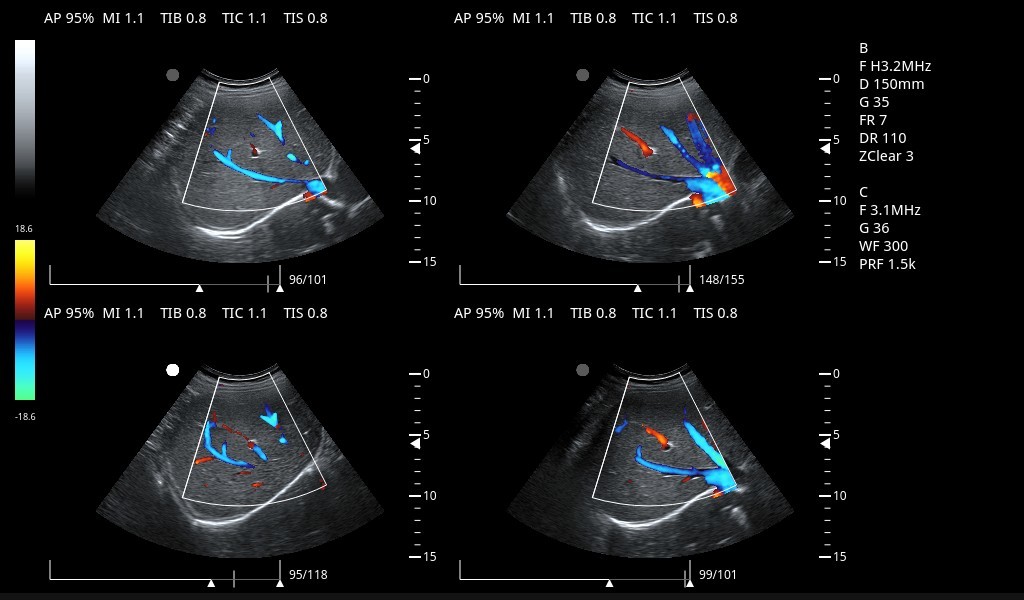

Excelentes imágenes clínicas

|

|

|

|

|

|